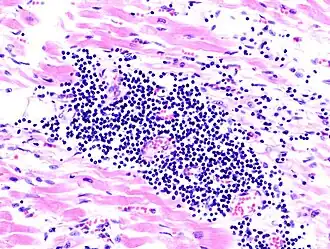

O imagine la microscop a miocarditei la autopsie la o persoană cu debut acut de insuficiență cardiacă